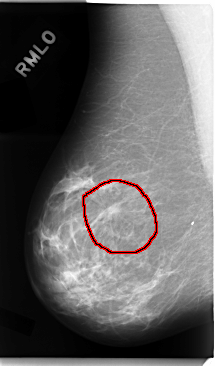

C_0034_1.RIGHT_MLO

RIGHT_MLO LINES 4752 PIXELS_PER_LINE 2792 BITS_PER_PIXEL 12 RESOLUTION 50 OVERLAY

FILE: C_0034_1.RIGHT_MLO.OVERLAY

TOTAL_ABNORMALITIES 1

ABNORMALITY 1

LESION_TYPE MASS SHAPE IRREGULAR MARGINS SPICULATED

ASSESSMENT 5

SUBTLETY 5

PATHOLOGY MALIGNANT

TOTAL_OUTLINES 1

BOUNDARY